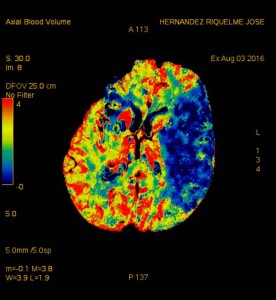

Efectivamente, se ve una estenosis por trombosis en la arteria cerebral media izquierda, que es la causa de el infarto isquémico agudo.

La primera prueba que se hace es la TAC simple, porque es la mas rapida y permite distinguir entre un infarto hemorragico y un infarto isquemico. Si el infarto es isquemico, como en este caso, se sigue con el angio-TAC que permite descubri la arteria implicada. Por fin se puede hacer un TAC perfusion para determinar la extension de la area isquemica.